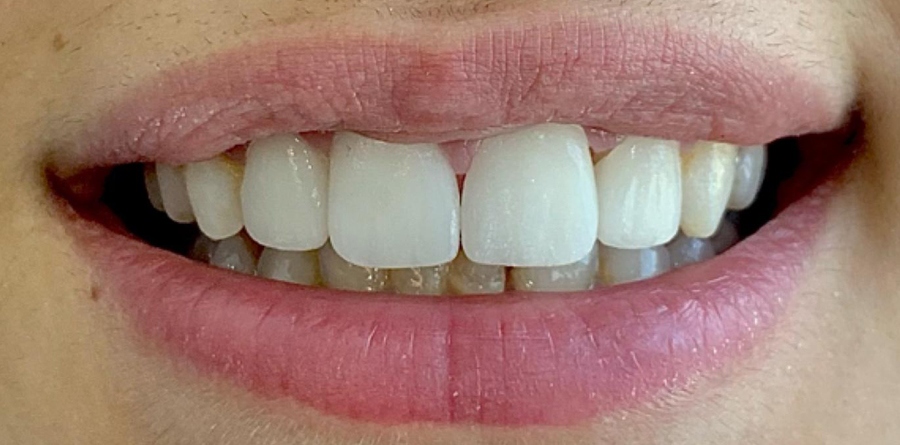

Vorher Nachher